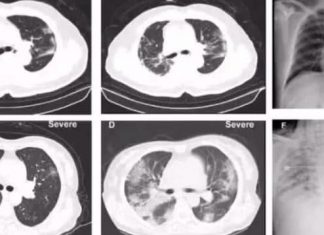

Ահա թե ինչ է կատարվում երբ վարակվում եք COVID19 –...

COVID19 մեծ աղետ է ամբողջ աշխարհի համար։ COVID19 տարածման 7֊8 (իսկ Հայաստանում 3,5) ամիսների ընթացքում անընդհատ ի հայտ են գալիս մի շարք նոր կլինիկական...